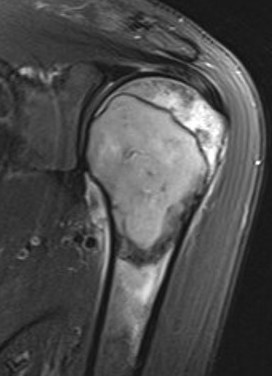

MRI

Low signal intensity T1 / high signal intensity T2

Areas of ABC seen in 10 - 14%

Look for signs of grade III: soft tissue extension